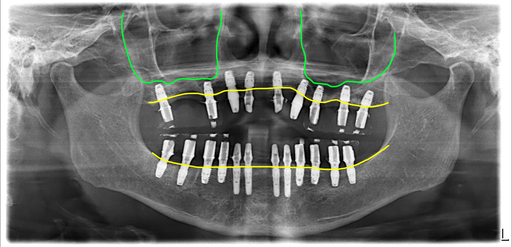

교합적응후 지르코니아 보철로 교체

2차 하러 오신 날 최종보철의 형태를 임시치아 재료로 끼고 잘 생활하시다가 3개월 체크할 때 환자분이 편안하다고 하셔서 미리 만들어 놓은 지르코니아 보철로 교체해서 세팅한 모습입니다.

4회 내원 치료기간 5개월 전체임플란트 치료완료

전체 내원 4회로 최종보철의 형태를 임시재료로 끼고 가셨고, 3개월 후 점검할 때 지르코니아로 교체해서 마무리가 되었습니다. 일단 수술 후 5개월째부터는 정상적인 식사가 가능하게 만들어 드렸어요.

전남 고흥에서 오신 60대 여성의 치료가 이렇게 잘 마무리되었고, 치료 끝난 지 1년반 정도되었네요. 1년에 한 번은 오셔서 검진을 해 달라고 부탁드렸어요.